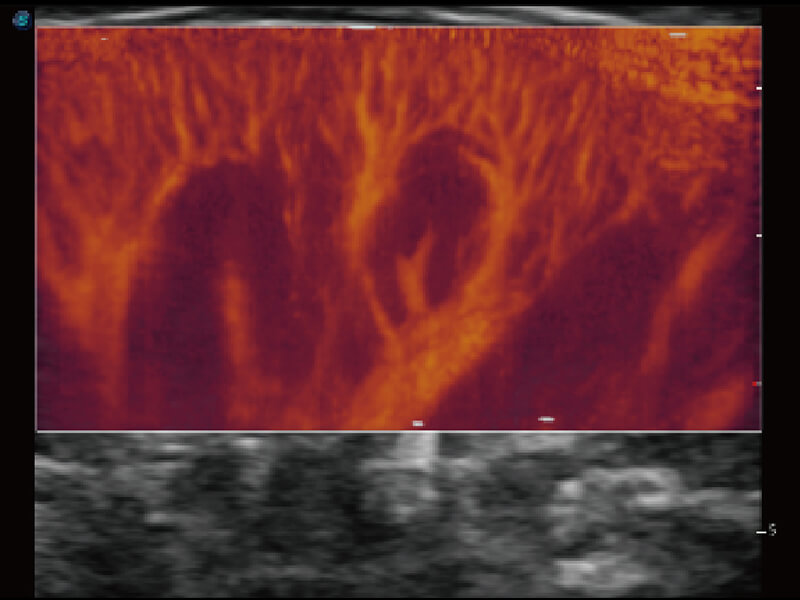

成像功能

S60探头工艺,从前端信号处理每一个环节采集无损声学数据,真实还原组织原貌,再现解剖细节。